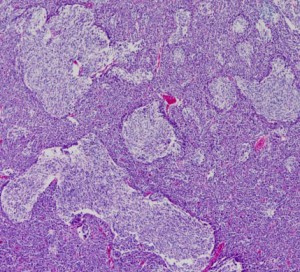

desmoplastic/nodular medulloblastoma

このタイプも治りやすい髄芽腫に分類されています。左がGFAP,右がsynaptophysinです。グリア系への分化を示すGFAPに染まる部分で細胞の増殖力が高くMIB-1の染色率も高いです。島状(結節状)になっていてsynaptophysinで染まる神経細胞への分化を示す部分では,細胞増殖割合は低いです。髄芽腫では神経細胞への分化が観察される分化型のもので治療反応性が良いと考えられます。

左は1歳児に発生した一部に神経芽細胞腫様の分化 row of the tumor cells (or neuronal differentiation) を伴う髄芽腫 medulloblastoma with extensive nodularity(小脳神経芽細胞腫 cerebellar neuroblastomaともいわれたもの)。右は7歳児の退形成(核の異形成)が顕著な退形成性髄芽腫 anaplastic medulloblastomaです。前者の治癒率は高く,後者の病理像の治癒率は極めて低いものです。